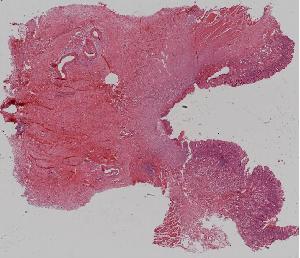

8. Granulation tissue